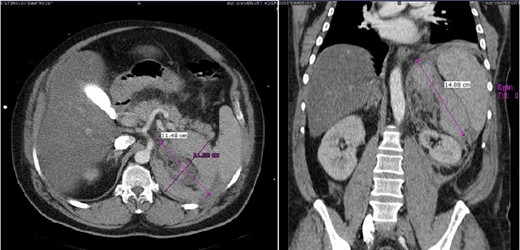

A 47-year-old male presented with, epigastric pain radiating to the back and profuse sweating. The patient was a smoker, obese and not on regular medication. Other than hypertension (BP: 210/120 mmHg), observations were normal. The abdomen was distended without rebound tenderness. Blood tests showed leukocytosis (WBC:12.000, 55% neutrophils), while hematocrit, platelets, coagulation profile and routine biochemistry were normal. Ultrasonography (US) was unremarkable, while computed tomography (CT) revealed a large retroperitoneal hematoma at the site of the left adrenal gland, with minimal contrast extravasation (Fig. 1). The patient was transferred to ICU, due to uncontrolled hypertension and suspicion of underlying pheochromocytoma, despite no obvious CT finding. The patient became hemodynamically unstable and Hct dropped to 35%. Angiography that followed showed no contrast extravasation. Further reduction of Hct to 22% necessitated transfusion with 2 units of blood. Subsequent CT showed stable hematoma without active bleeding. The patient was transferred to the ward after 8 days. Investigation for potential adrenal mass and post-hemorrhage adrenal insufficiency was commenced, requiring restricted diet for testing of urine vanillylmandelic acid (VMA). Blood cortisol and ACTH were normal, while investigation for exclusion of pheochromocytoma was inconclusive. Metaiodobenzylguanidine (MIBG) scan was negative. The patient was discharged with well-controlled blood pressure. On follow-up, urine VMA was reduced, while abdominal MRI, performed after 2 months, showed complete hematoma resolution and no underlying mass (Fig. 2).

Case 1 follow-up MRI showing almost complete resolution of the hematoma and absence of underlying adrenal lesion.